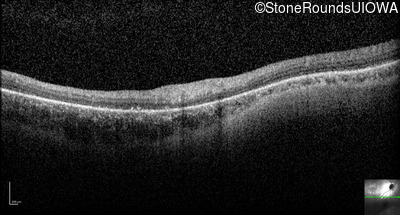

Optical Coherence Tomography - Right - 10/120 +1

Exemplar / OCT Stack